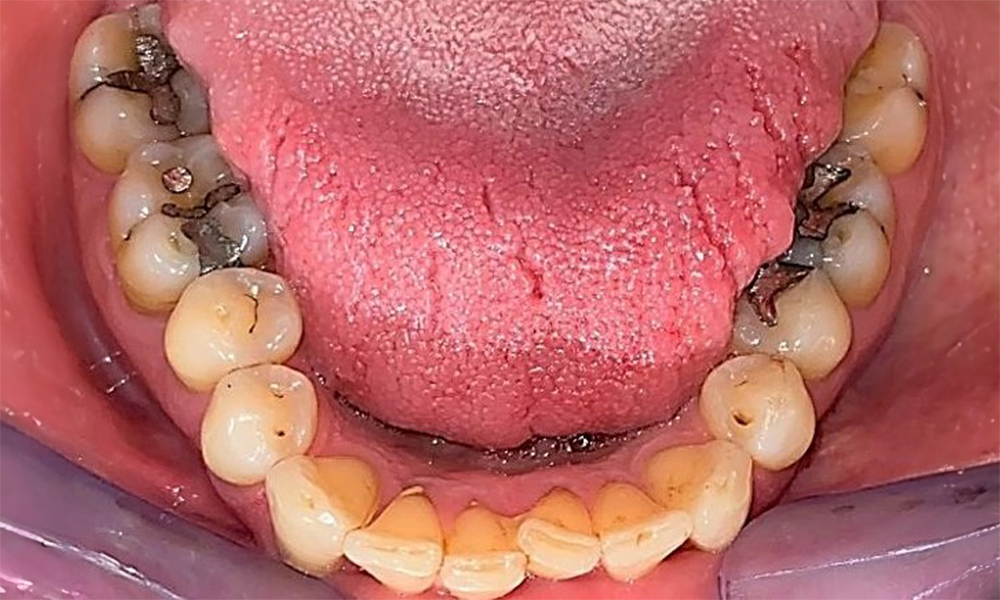

Occlusal view of the mandible showing the denture in situ.

Fig. 6 Occlusal view of the mandible showing the denture in situ. © Dr R. Krapf

The patient has a full dentition with 28 teeth, which includes amalgam and composite fillings in the molar and premolar regions. There is a visible clinical marginal gap present on tooth 14. Tooth 27 has an adequate gold inlay. There are also generalized attritions and abrasions. (Fig. 2, Fig. 3, Fig. 4, Fig. 5, Fig. 6)

The patient has stage II, grade B periodontitis (5). At 1 to 3 mm, the clinical probing depths were within the physiological range. Localized probing depths of 5 mm were observed on the mesiopalatal aspects on both 17 and 27. There are generalized recessions of 1–3 mm with partial loss of the interdental papillae (Fig. 2, Fig. 3, Fig. 4)